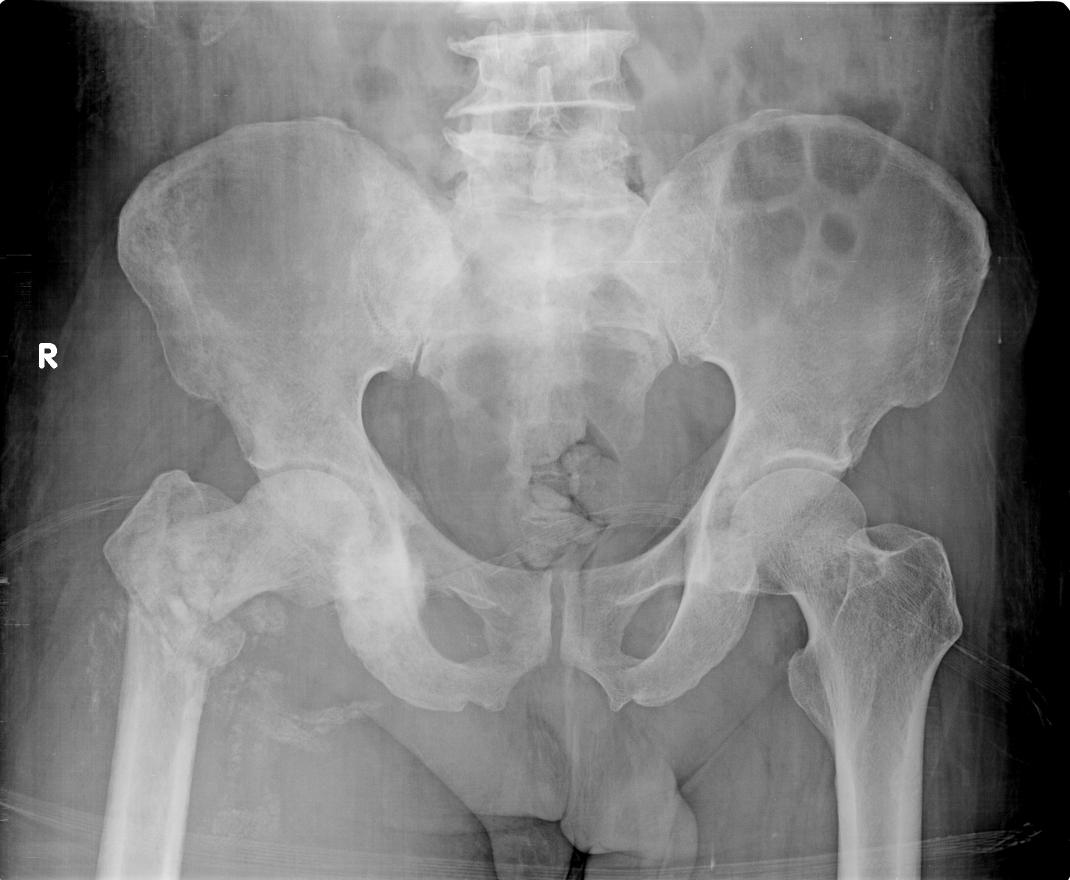

男,56 岁.右髋疼痛10年余,否认外伤史

右股骨陈旧性转子间骨折

右股骨粗隆间陈旧性骨折并骨化性肌炎

考虑病理性骨折机率大(因为1病人成年人,否认外伤病史2右髋关节间隙较对侧密度内圆形增浓)。建议进一步检查。

右侧股骨粗隆间陈旧性粉碎性骨折并骨化骨肌炎。建议:行进一步检查排除病理性骨折可能。

考虑病理性骨折---软组织肿胀,股骨肌间脂肪线消失

本人觉得病理性骨折应该肯定原因有:

1:股骨转子间骨折,不是一般的磕碰,正常成人应能非常明确的记得外伤史。

2:右侧软组织明显肿胀,如单纯外伤骨折,十年病史,肌肉应废用萎缩。

3:如单纯外伤骨折,十年病史,应有大量骨痂形成,如骨不连应有假关节形成,但本片断端髓腔并未闭合。

4:右侧髂骨外缘密度增高,结构较模糊,不排除受累。